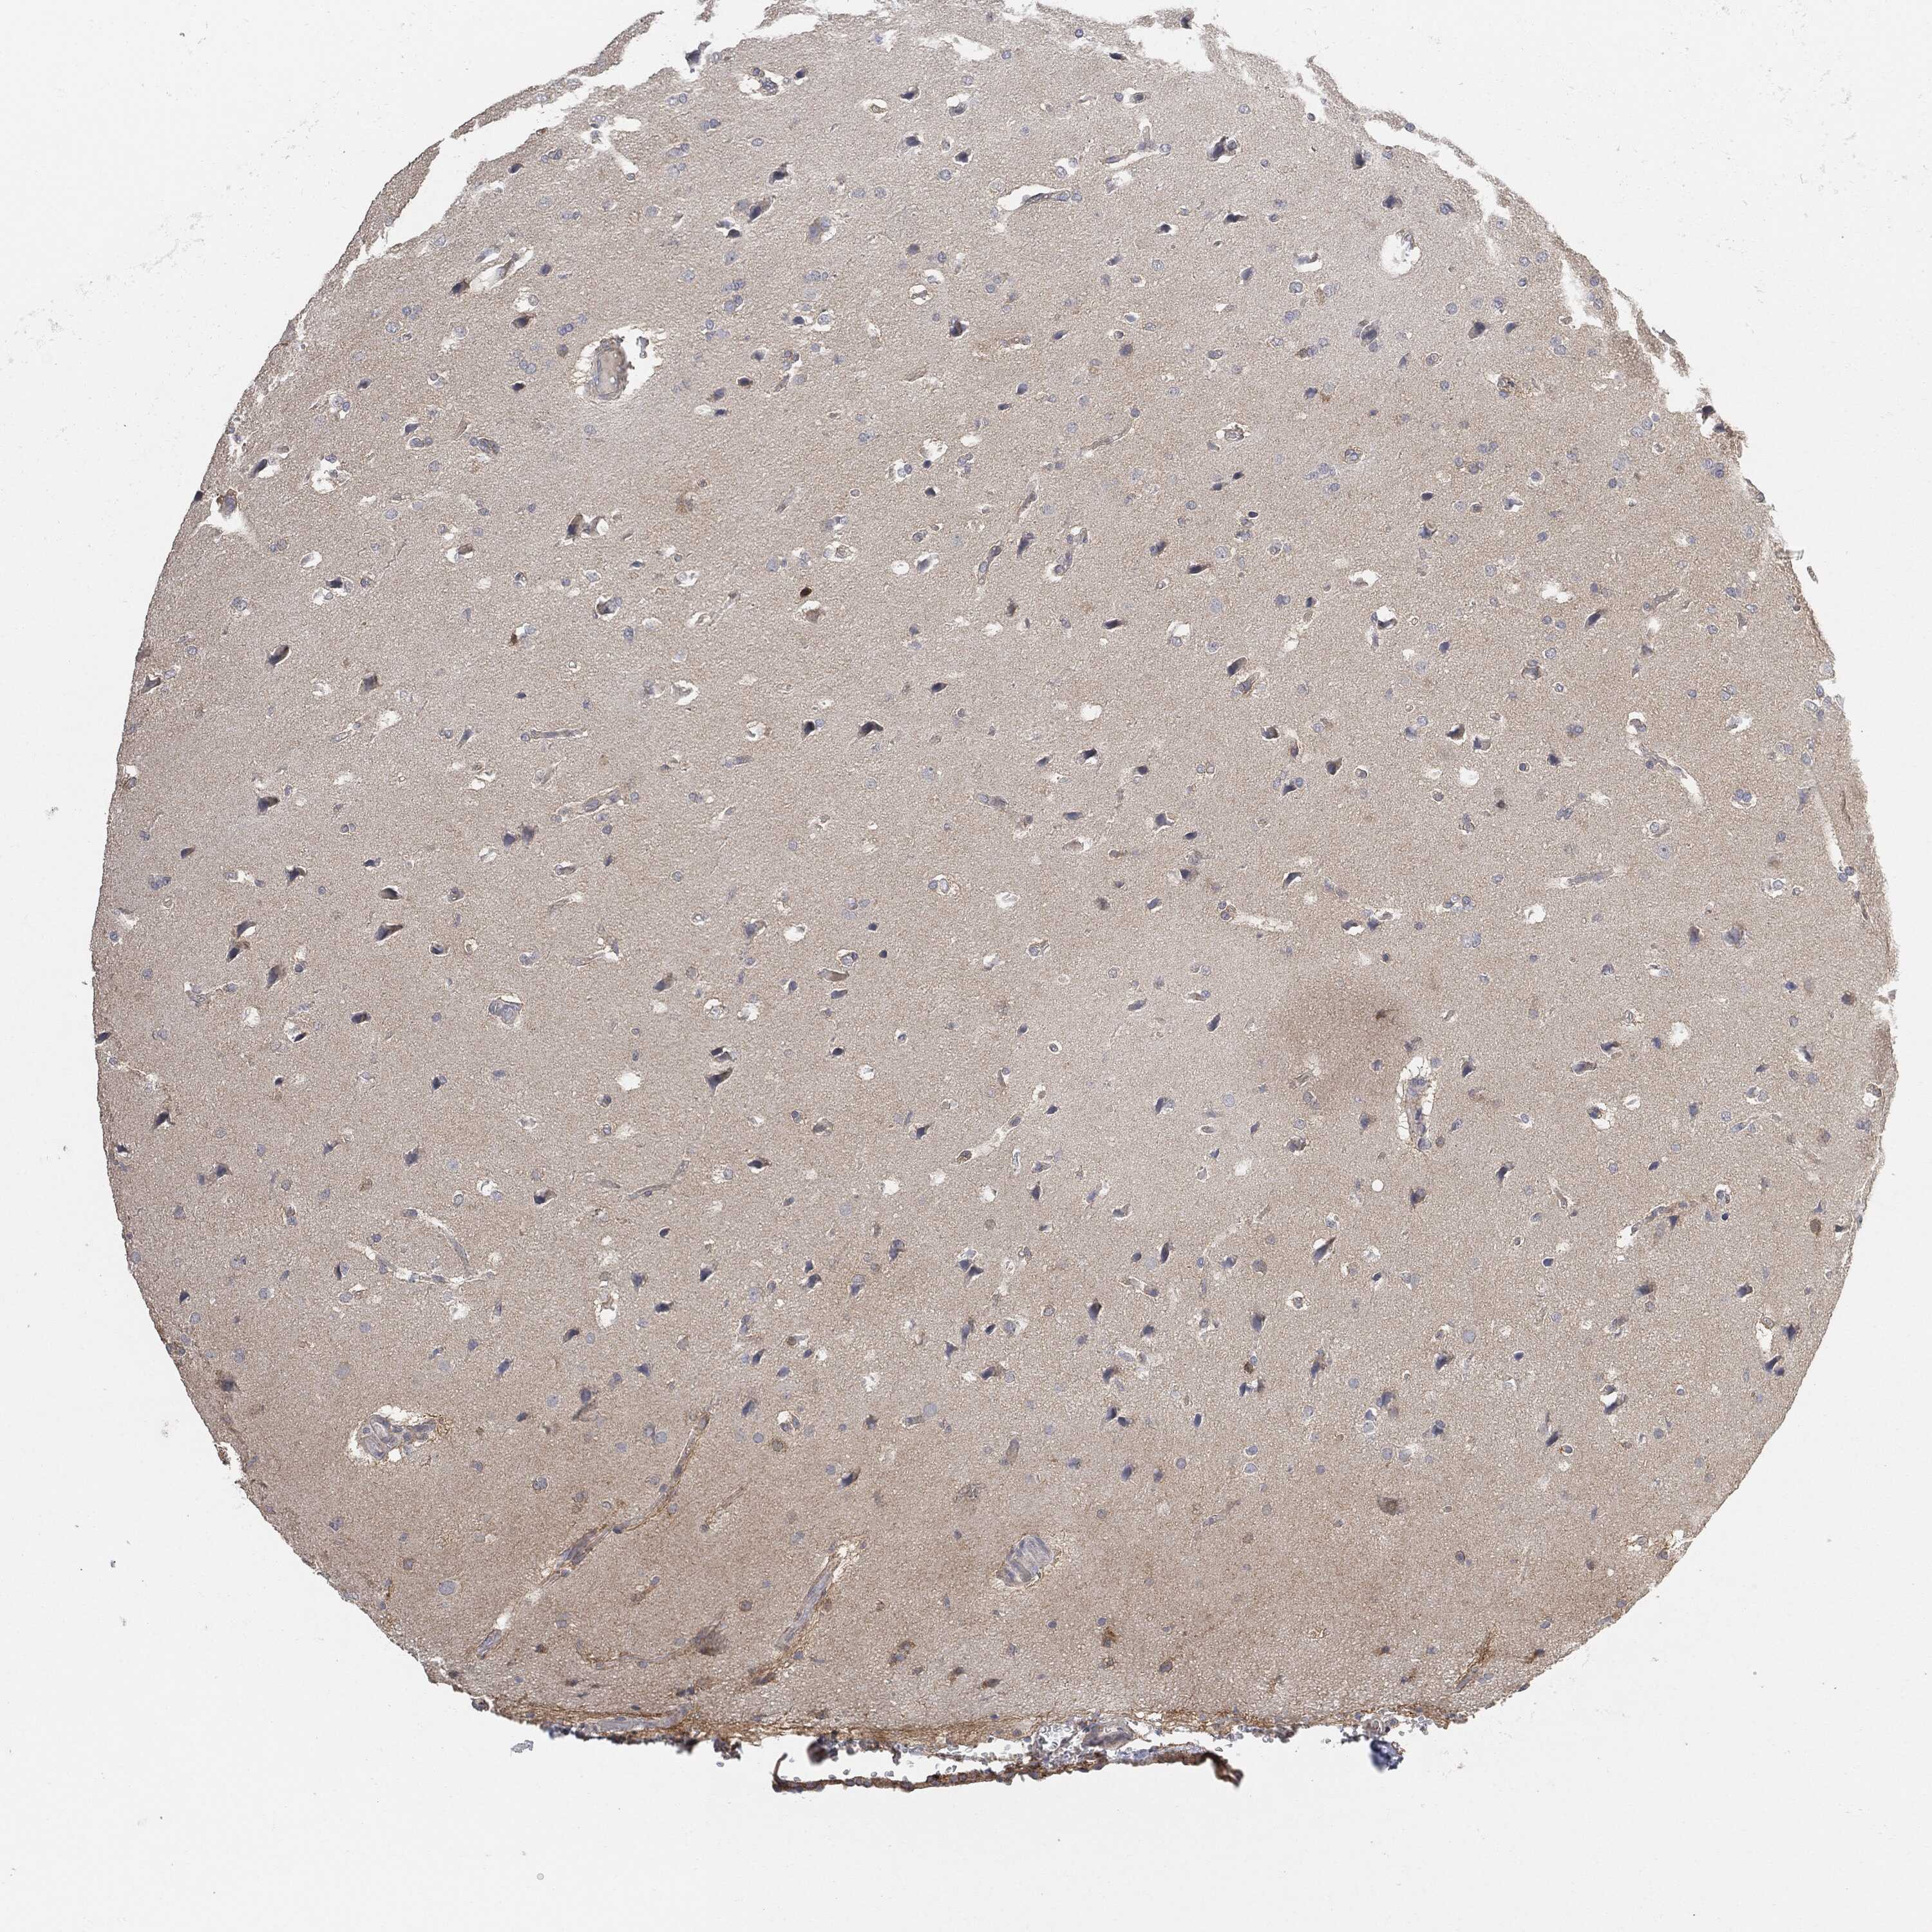

GLIOMA - Protein expressioni

A mouse-over function shows sample information and annotation data. Click on an image to view it in a full screen mode. Samples can be filtered based on level of antibody staining by selecting one or several of the following categories: high, medium, low and not detected. The assay and annotation is described here.

Note that samples used for immunohistochemistry by the Human Protein Atlas do not correspond to samples in the TCGA dataset.

Antibody stainingi

Antibody staining in the annotated cell types in the current human tissue is reported as not detected, low, medium, or high, based on conventional immunohistochemistry profiling in selected tissues. This score is based on the combination of the staining intensity and fraction of stained cells.

Each image is clickable and will lead to virtual microscopy that enables deeper exploration of all samples and also displays staining intensity scores, fraction scores and subcellular localization as well as patient and tissue information for each sample.

Glioma, malignant, High grade

Glioma, malignant, Low grade

Glioma, malignant, NOS